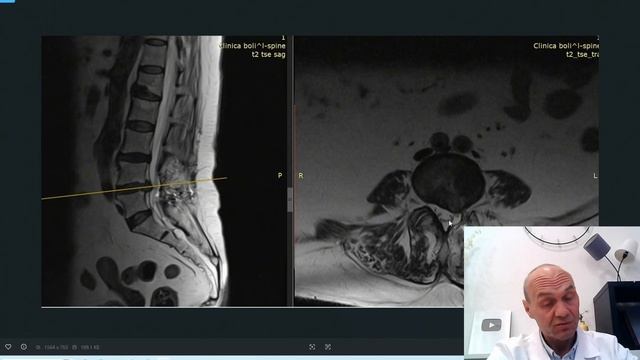

Здравствуйте! Если Ваша проблема трудна для решения и лечение не помогает Вы можете связаться с нами онлайн. Как это работает? Для записи позвоните по телефону: 7484221-00-00 Администратор расскажет вам куда прислать снимки и данные исследов..., видео от 2026-02-19 загрузил на rutube bezboli...